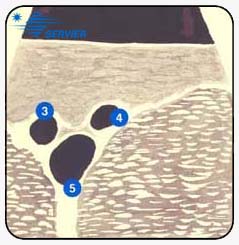

Вид на ультрасонографии типичен в этом месте и представлен на

(Рисунок

60-B). На поперечной секции, при установке датчика вдоль паховой

складки, картина "Mickey Mouse" наблюдается. бедренная вена (от 10 до

15 мм

диаметром) формирует лицо, бедренная артерия (6 мм) и БПВ (от 3 до 5 мм) формирует

два уха.